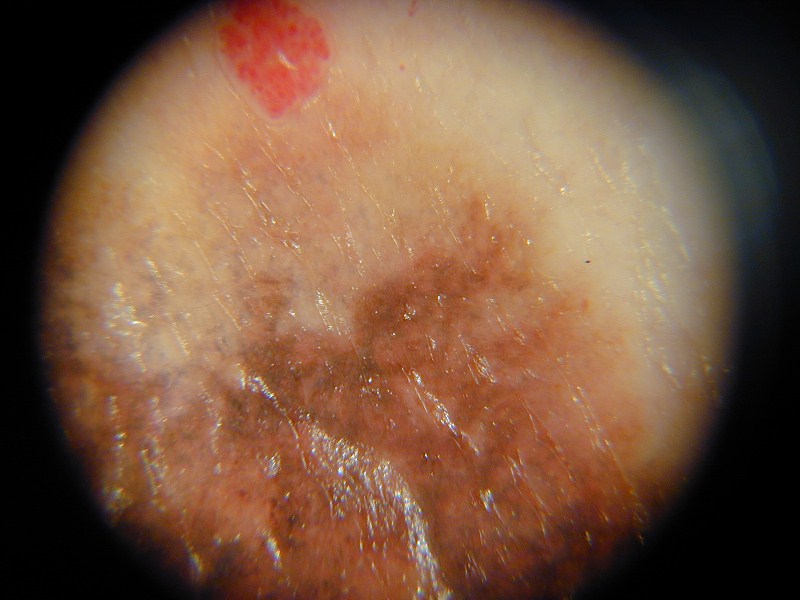

Nevo melanocitico (dermatoscopia)

Melanoma a diff. superficiale (dermatoscopia)